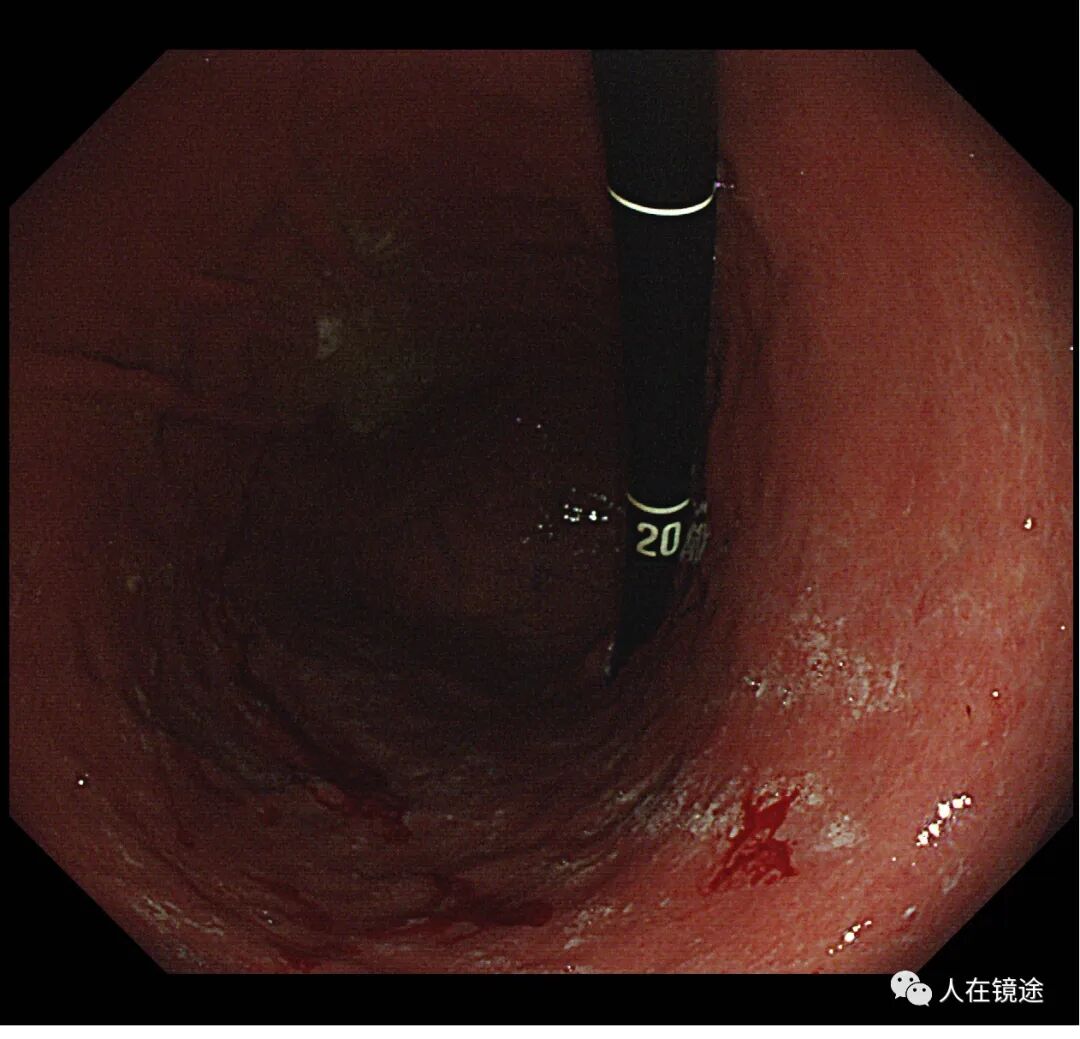

胃体下部小弯粘膜红白相间,以白为主,RAC消失